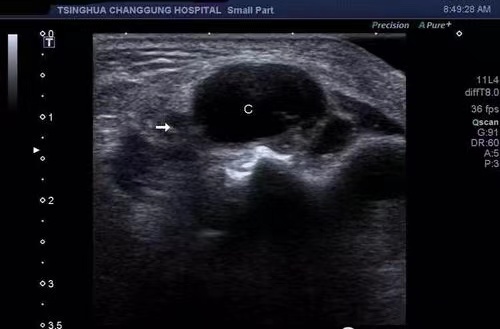

今年1月份,我院功能科在全市率先開展胃腸超聲檢查新業(yè)務(wù)。截至目前胃超聲共檢查170余例,腸道超聲檢查10余例,深受廣大患者好評。

胃腸超聲是指患者口服助顯劑充盈胃腸后,排除胃腔及腸道內(nèi)氣體和黏液,清晰地顯示胃腸壁層次結(jié)構(gòu)以及病變的超聲檢查方法。我院功能科副主任醫(yī)師楊赟在協(xié)和醫(yī)院進(jìn)修學(xué)習(xí)后,掌握該項(xiàng)技能。

胃超聲與普通胃鏡的區(qū)別就是能看到胃壁里面的結(jié)構(gòu),發(fā)現(xiàn)胃壁腫瘤的部位、大小和形態(tài),對粘膜下、肌壁間病變及外侵性病變有優(yōu)勢。胃超聲與胃鏡檢查相輔相成,取長補(bǔ)短,提高了胃部疾病檢查診斷的全面性和準(zhǔn)確性。腸道超聲檢查可以觀察到小腸、結(jié)腸及直腸的腸壁厚度、層次結(jié)構(gòu)、腸腔狹窄或擴(kuò)張,以及腸外的病變,成為腸道疾病的有效診斷方法。